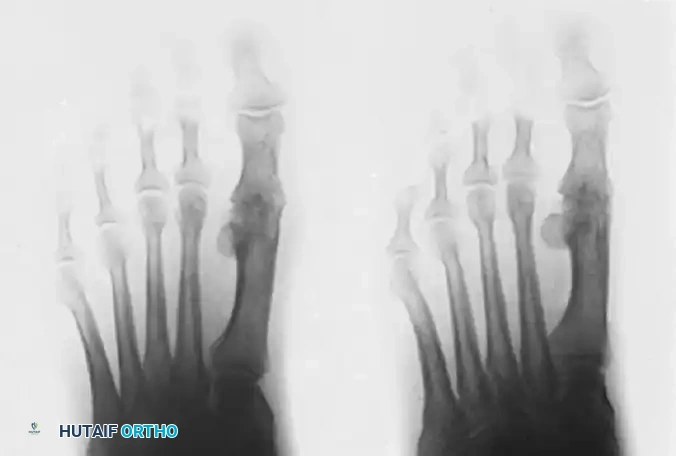

Image

Anteroposterior view of bilateral hallux rigidus, highlighting the symmetric nature of the degenerative process in susceptible individuals.